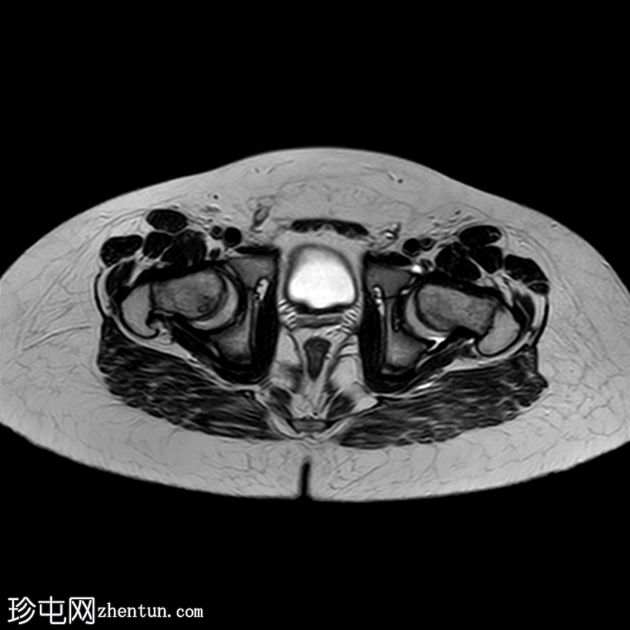

MRI

轴位片

T2加权像

双侧股骨近端骨骺皮质不规则,轻度增宽,伴股骨骨骺及近端干骺端骨髓水肿。

双侧股骨骨骺轻度后内侧移位。

双侧轻度髋关节积液。